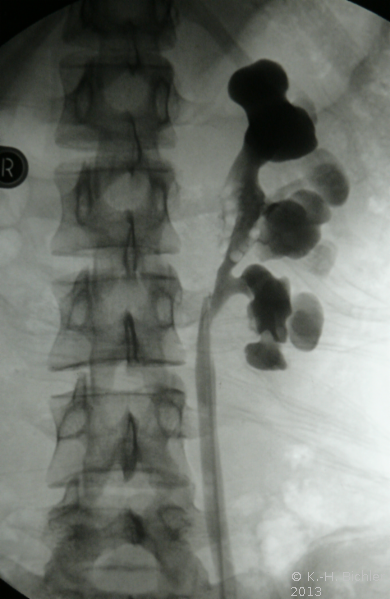

- Abbildung: Ureterabgangsstenose links bei 15jährigem Mädchen

- b) Retrograde Sondierung postoperativ

Retrogrades Pyelogramm